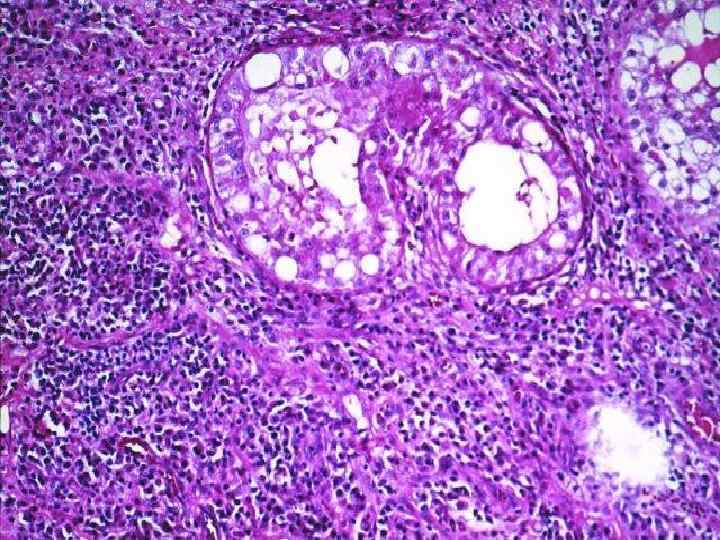

Семинома